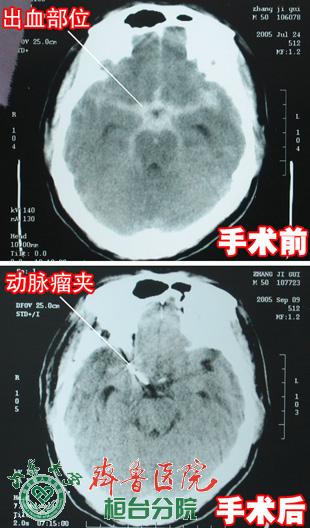

近日,齐鲁医院桓台分院(桓台县人民医院)神经外科收治了一名巨大脑动脉瘤病人,该病经过孙冲主任的检查和确诊,并且组织详细的术前讨论,制定了严密的手术方案和充分的术前准备,于2008年5月10日,由孙冲主任主刀,经过3个多小时精心细致的手术,为病人成功实施了脑动脉瘤夹闭术,解除了病人潜在的脑动脉瘤再次出血危险。

脑动脉瘤破裂出血发病急,出血量大,症状重。脑动脉瘤若得不到有效治疗在3个月内脑出血致死率达81%,40%是因为二次出血。尽早明确诊断,尽早外科治疗(手术夹闭或介入栓塞)是防治脑动脉瘤出血,挽救病人生命的关键。脑动脉瘤破裂后手术夹闭是神经外科难度大、风险高的手术,术中脑动脉瘤破裂大出血往往难以控制,非常凶险。我院神经外科在介入室、神经内科的协作下,近二年来,已成功实施脑动脉瘤破裂出血急性期夹闭手术5例,未发现手术并发症和复发,均痊愈出院,病人非常满意。